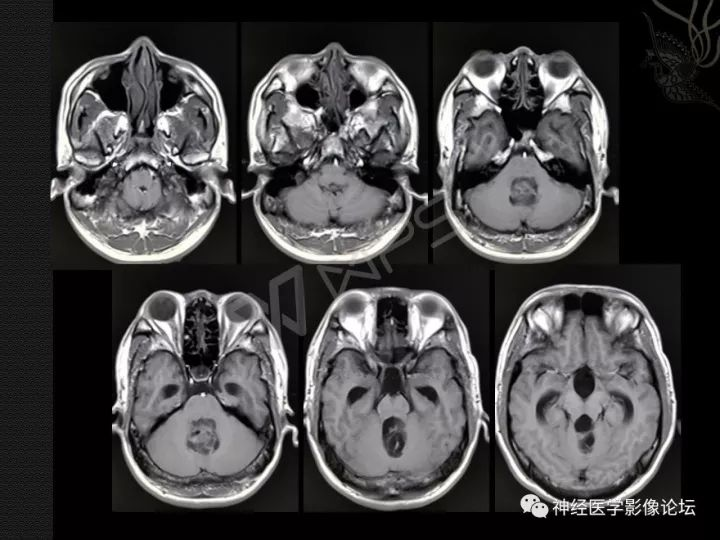

大多数中央神经细胞瘤是多囊性肿瘤且有钙化,以宽基底附着在脑室上外侧壁上。它们通常位于侧脑室或三脑室,附着于室间孔附近的透明隔或脑室壁上。但通常不会出现在侧脑室枕角或颞角。

典型的CT表现是脑室内不均匀的高密度肿块,伴有中等对比增强。MRI T1加权像表现为轻度高信号,T2加权像表现在某种程度上更加多变。使用钆后通常增强。可能难以通过MRI区分中央神经细胞瘤、脑室外神经细胞瘤与更常见的病灶(像高级别胶质瘤)。